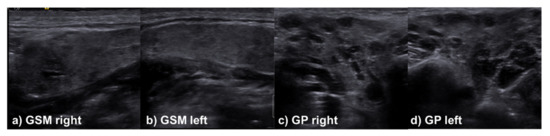

2.3. Sonographic Evaluation